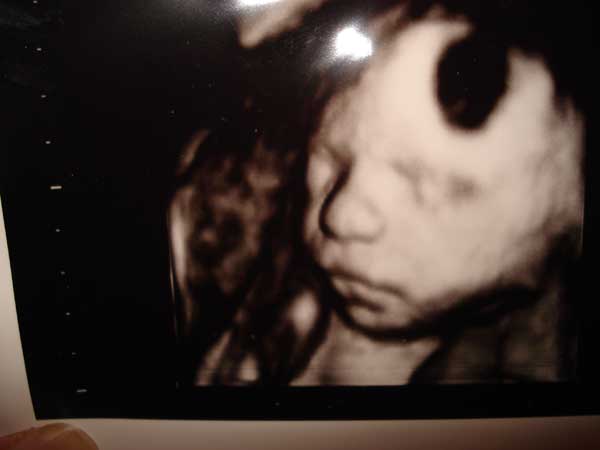

Ezt a képet kaptuk:)